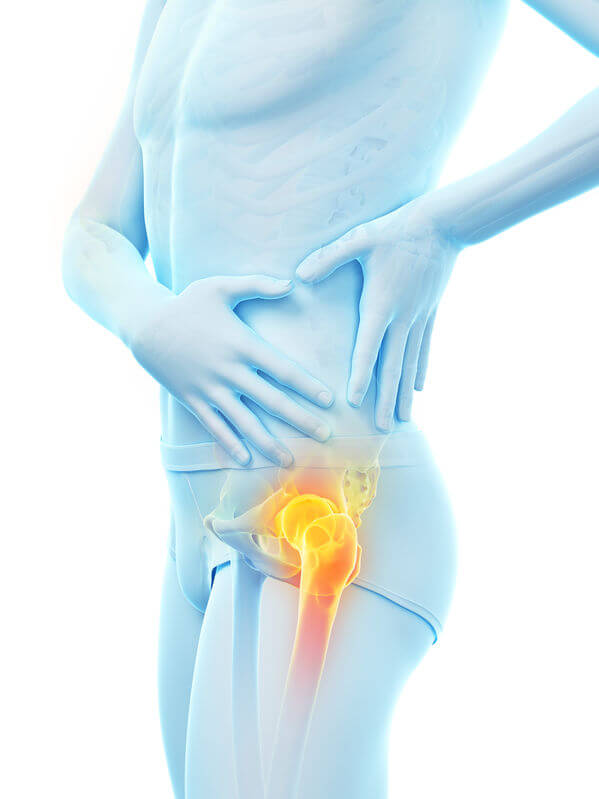

腰の痛み- 「あぐらをかくと股関節が痛い」女性に多い理由とは?